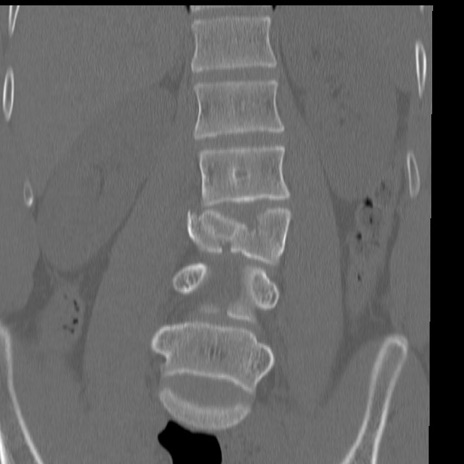

症例3 腰椎CT(冠状断像)

腰椎CT

横断像